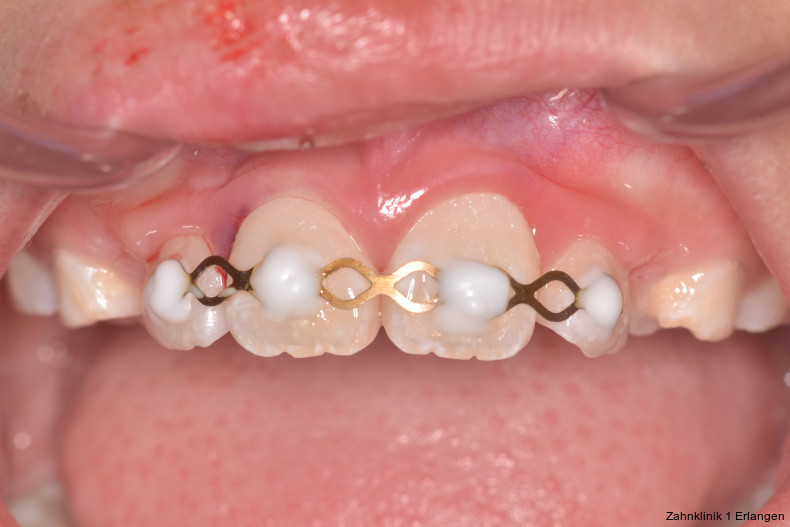

Versorgung von Dislokationsverletzung

Bei ausgeprägten Dislokationsverletzungen stellt die Schädigung des Parodonts die dominierende Verletzung dar, die auch zu Spätfolgen und Komplikationen führen kann. Verletzungen des Endodonts sind im Hinblick auf den Zahnerhalt vergleichsweise unbedeutender, da die Wurzelkanalbehandlung eine Infektion relativ sicher verhindern oder beseitigen kann. Die Erstversorgung schließt im Wesentlichen die Repositionierung und Schienung zur Ruhigstellung der betroffenen Zähne ein.3 Spätestens ab einer Positionsveränderung von 2 mm ist bei Zähnen mit abgeschlossenem Wurzelwachstum sicher von einem irreparablen Schaden der Pulpa auszugehen.2 Wichtig ist es, zeitnah, in der Regel während der Schienungsdauer, die Wurzelkanalbehandlung einzuleiten, um eine bakterielle Besiedelung des Wurzelkanals zu verhindern. Dabei reicht es zunächst aus, den Zahn zu eröffnen, desinfizierend zu spülen und eine medikamentöse Einlage einzubringen. Wird dies unterlassen, entwickeln sich bei entsprechender parodontaler Schädigung infektionsbedingte Resorptionen, die rasch fortschreiten und innerhalb relativ kurzer Zeit bis zum Zahnverlust führen können.